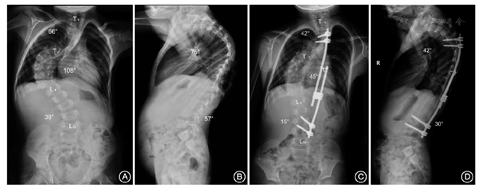

选择1例EOS患者(男,7岁,特发性脊柱侧凸,身高100 cm,体质量15 kg)作为研究对象。患者脊柱侧凸主弯为右胸弯(Cobb角108°),上胸弯(Cobb角66°),腰弯(Cobb角38°)。术前Bending像显示主弯可矫正至99°(韧度8.3%)。术后影像显示主胸弯矫正至45°(矫正率58.3%),上胸弯矫正至42°(矫正率36.4%),腰弯矫正至15°(矫正率60.5%)。术前、术后胸椎T2~T12后凸角分别为75°和42°,腰椎L1~S1前凸角为57°和30°(图1)。

注:术前脊柱全长正侧位X线片(A,B):主胸弯Cobb角108°,上胸弯66°,腰弯38°,胸椎后凸75°,腰椎前凸57°。单侧生长棒固定术后脊柱全长正侧位X线片(C,D):主胸弯Cobb角45°,上胸弯42°,腰弯15°,胸椎后凸42,腰椎前凸30°